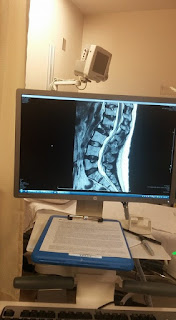

I got back to the house, Eric had breakfast and we were off to exchange an item we got at a store and then off to the hospital for my procedure. As the time got closer, I wasn't just excited, but I was nervous at the same time. I think I was nervous about the possible pain (which I know would be nothing compared to the pain was dealing with on a day to day basis already) and the possibility that the cement could go where it shouldn't go and get in my bloodstream that goes to my lungs. All of which are probable but not necessarily possible. We sat, waiting to be admitted. Really, to check me in. After I was all checked in, we waited a few minutes for my nurse and then she took us down to the basement where the procedure would take place. I should say, this wasn't at the regular Kaiser hospital we go to in Roseville. This took place at the older Kaiser hospital in Sacramento. So, a lot of procedure rooms and doctors offices are in the basement. I got changed into my hospital gown and got my hair net thing on and my nurse started to take my pulse, temperature and blood pressure. After that was all done, she got my IV started. Where I would get fluid and the medicine to help kind of knock me out. She went to get the doctor so he could explain the procedure. He came in, explained what he was going to do and what the side effects could be. He also showed us my MRI from not long ago which showed the vertebrae that was going to get the cement. It was my L2. You can see the difference in that vertebra compared to the rest. It's almost like it was disintegrated. Eric got a picture for me since I had already given him my purse with phone in it to take with him while I had the procedure done.

My back, before

My back before and after, before on left, after on right

The nurse called Eric to come back down so I could be discharged and the doctor came in and showed me the difference in the MRI's. Basically, the before and the after. It's amazing the difference in my vertebrae. Although, it may look like it would give me some height back, the procedure does not do that. Too bad. Guess I will be 5'4" from now on. All I can do is stand tall and make myself look taller. Hehe! I will say, I didn't feel any bone pain at this point. The only thing I felt at this point was the bandage. It felt/feels weird where it's at. It will stay there for a while. I was told I could shower but I could not take a bath for a while, until the small hole has healed up where the needle went in to put the cement in my back.